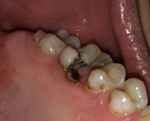

Восстановление зуба из 1 стенки

Если у вас осталась одна стенка зуба, можно ли восстановить ее – вопрос несложный. С помощью искусственной коронки можно восстановить большую часть зуба и предохранить его от дальнейшего разрушения. Применение штифтов целесообразно только в случае, если повреждены резцы или клыки, так как на жевательные зубы приходится большая нагрузка и штифты не смогут с ней справиться. Кроме того, коронка – более надежна, особенно в случае, когда от вашего зуба осталось меньше половины.

Осталась одна стенка зуба

После повреждения осталась лишь одна стенка? Такая ситуация не особо критична, ровно как и если у вас откололась небольшая часть зуба (рекомендуем прочитать: что делать, если кусочек зуба откололся?). В таких случаях восстановить здоровье десны и зубов можно с помощью:

- использования коронки,

- полного наращивания с использованием штифтов.

В варианте с наращиванием вам придется платить за штифты и материал, соответственно цена будет зависеть от материала. Чем хорош такой способ? После наращивания зуб будет выглядеть как родной и иметь идеальную форму, нервные каналы и корень зуба будут защищены от воздействия внешних факторов. При использовании высококачественных материалов данная конструкция никогда не отломится.